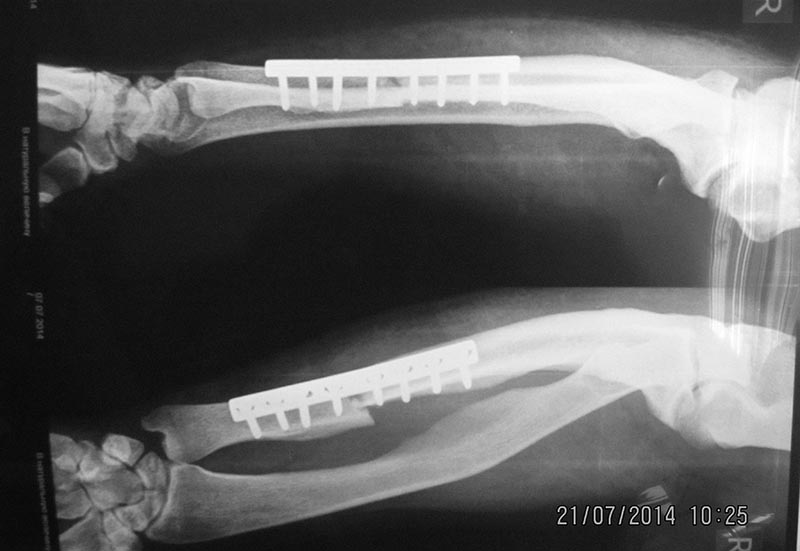

[Ortho] перелом бедра с исходной деформацией

Выкладываю, как и обещал. За репозицию педплечья не осуждайте!